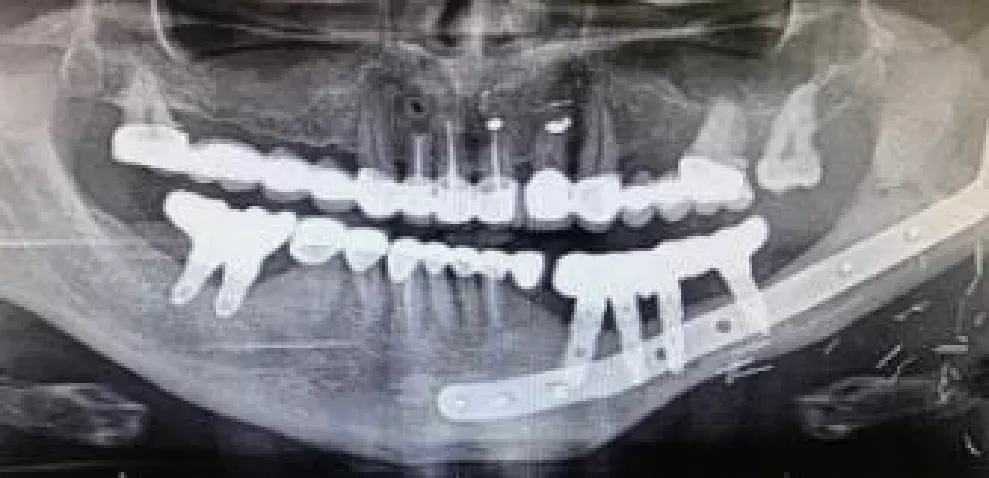

| Mandibular right body and ramus ameloblastoma | Segmental mandibulectomy | Fibula flap | sCAIS | 2 flap, 1 failed | Fixed screw retained | ![]() |

| Right mandibular body epidermoid carcinoma | Segmental mandibulectomy and neck dissection | Double-barrel fibula flap | dCAIS | 3 flap | Fixed screw retained | ![]() |

| Left mandibular body epidermoid carcinoma | Segmental mandibulectomy and Neck dissection | Iliac crest free flap | dCAIS | 2 flap | Fixed screw retained | ![]() |

| Left mandibular body ameloblastoma | Segmental mandibulectomy | Fibula flap | dCAIS | 4 flap | Fixed screw retained | ![]() |

| Right mandibular body ameloblastoma | Segmental mandibulectomy | Fibula flap | dCAIS and freehand | 3 flap | Fixed screw retained | ![]() |

| Hard palate adenoid cystic carcinoma | Central maxillectomy | Radial forearm flap | dCAIS and sCAIS | 5 Mx | Fixed screw retained | ![]() |

| Left maxilla tuberosity adenocarcinoma | IIb Brown maxillectomy | Iliac crest free flap | dCAIS and sCAIS | 3 flap | Fixed screw retained | ![]() |

| Left mandibular body epidermoid carcinoma | Segmental mandibulectomy and Neck dissection | Double-barrel fibula flap + 70 Gy | dCAIS and sCAIS | 3 flap | Fixed screw retained (Pending) | ![]() |

| Left mandibular body epidermoide carcinoma | Segmental mandibulectomy and Neck dissection | Fibula flap | dCAIS and sCAIS | 3 flap | Fixed screw retained (pending) | ![]() |

| Right hemitongue epidermoid carcinoma | Hemiglosectomy, bilateral neck dissection | Alt+ Vastus Lateralis Flap + 70 Gy | dCAIS | 6 mx | Fixed screw retained (pending) | ![]() |

| Left hemimandible ameloblastoma | Segmental mandibulectomy | Failed Fibula flap and pectoralis major | sCAIS | 5 mx | Fixed screw retained (pending) | ![]() |